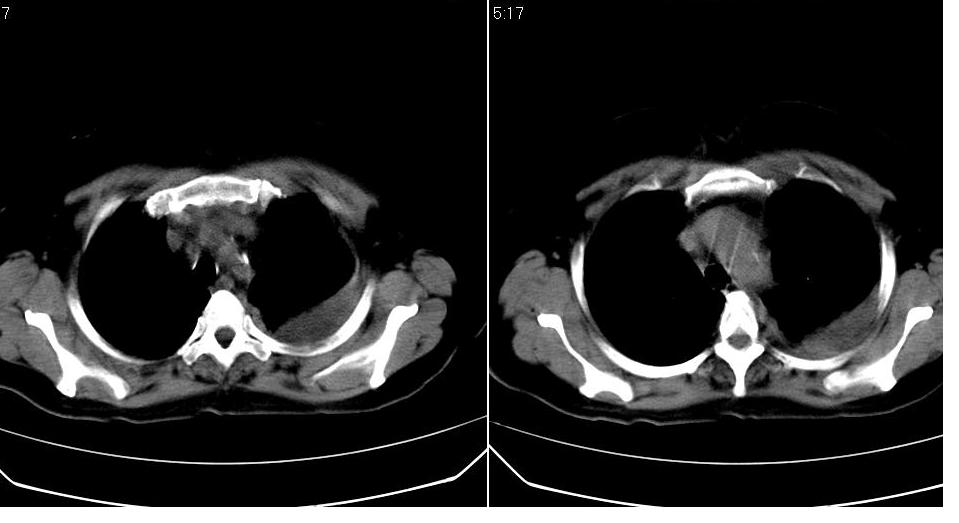

女 59岁,胸背疼,不咳嗽,不咳痰,不发热。

1)考虑左肺下叶背段周围型肺癌并左肺下叶及左侧胸膜转移。2)左侧胸腔积液。3)左冠状动脉钙化。

1)考虑左肺下叶背段周围型肺癌(腺癌可能性大)并左肺下叶及左侧胸膜转移。2)左侧胸腔积液。3)左冠状动脉钙化。